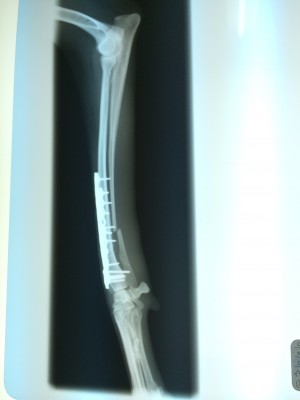

でもこれにも先生から説明があり『今回の手術はギブス固定ではなく、プレート2枚を使いしっかり固定をしているのでギブスは必要ありません。ギブスをしてしまうと、血流が悪くなること、自宅で患部の状況が解らないこと、骨折した足をほとんど使わないケースがあり筋肉が弱くなることもあるので必要なけでば使用しません』

そして詳しい手術経過の説明をして下さいました。今回の骨折は関節に近い部分であった為、より固定を安定させる為にプレートを2枚にしました。レントゲン写真を見ながら説明をして下さいました。(もちろん写真撮影は先生に許可を頂いてから行っています)

レントゲン写真を観た時は本当に可哀想になりました。。。痛かったね。。。

今後の経過ですが、状況を見ながらになりますが、3か月後ぐらいに大きいプレートを除去する手術をしますので、3週間毎に診察にきて下さい。ただし、術後は傷の化膿がありますので、テープに血や漿液(しょうえき)が滲んだら交換に来て下さい。